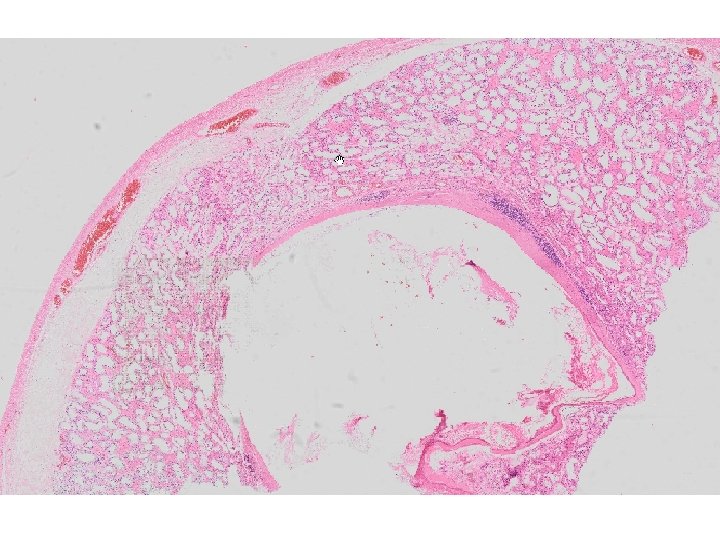

Makroskopické vyšetření • dodán materiál RAOE l. sin. • varle velikosti 48 x 27 mm • v horním pólu ohraničené bělavobéžové ložisko velikosti 18 x 16 x 15 mm, tvořené fokálně se oddrolujícími béžovými poloměkkými hmotami • ložisko bylo zablokováno celé

Mikroskopické vyšetření • tkáň varlete se stěnou cysty tvořenou různě silným hyalinizovaným vazivem s různě intenzivní kulatobuněčnou zánětlivou celulizací, která je ložiskově vystlaná zachovalým rohovějícím vrstevnatým dlaždicovým epitelem • v lumen cystického útvaru keratinové hmoty • v okolí cystického útvaru atrofické a hyalinizované semenotvorné kanálky

teratom prepubertálního typu (nezávislý na intratubulární germinální neoplázii), tzv. epidermální cysta